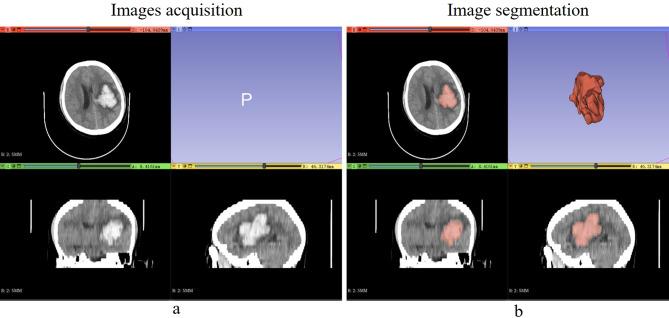

In hypertensive intracerebral hemorrhage (HICH) patients, while emergency surgeries effectively reduce intracranial pressure and hematoma volume, their significant risk of causing postoperative rehemorrhage necessitates early detection and management to improve patient prognosis. This study sought to develop and validate machine learning (ML) models leveraging clinical data and noncontrast CT radiomics to pinpoint patients at risk of postoperative rehemorrhage, equipping clinicians with an early detection tool for prompt intervention. The study conducted a retrospective analysis on 609 HICH patients, dividing them into training and external verification cohorts. These patients were categorized into groups with and without postoperative rehemorrhage. Radiomics features from noncontrast CT images were extracted, standardized, and employed to create several ML models. These models underwent internal validation using both radiomics and clinical data, with the best model's feature significance assessed via the Shapley additive explanations (SHAP) method, then externally validated. In the study of 609 patients, postoperative rehemorrhage rates were similar in the training (18.8%, 80/426) and external verification (17.5%, 32/183) cohorts. Six significant noncontrast CT radiomics features were identified, with the support vector machine (SVM) model outperforming others in both internal and external validations. SHAP analysis highlighted five critical predictors of postoperative rehemorrhage risk, encompassing three radiomics features from noncontrast CT and two clinical data indicators. This study highlights the effectiveness of an SVM model combining radiomics features from noncontrast CT and clinical parameters in predicting postoperative rehemorrhage among HICH patients. This approach enables timely and effective interventions, thereby improving patient outcomes.

在高血压性脑出血(HICH)患者中,尽管急诊手术能有效降低颅内压和血肿体积,但其术后再出血风险较高,因此需要早期检测和处理以改善患者预后。本研究旨在开发并验证利用临床数据和非增强CT影像组学来精准识别术后再出血风险患者的机器学习(ML)模型,为临床医生提供早期检测工具以便及时干预。该研究对609例HICH患者进行了回顾性分析,将其分为训练组和外部验证组。这些患者被分为有术后再出血和无术后再出血两组。从非增强CT图像中提取影像组学特征,进行标准化处理,并用于创建多个ML模型。这些模型使用影像组学和临床数据进行内部验证,通过Shapley加性解释(SHAP)方法评估最佳模型的特征重要性,然后进行外部验证。在对609例患者的研究中,训练组(18.8%,80/426)和外部验证组(17.5%,32/183)的术后再出血率相似。识别出六个显著的非增强CT影像组学特征,支持向量机(SVM)模型在内部和外部验证中均优于其他模型。SHAP分析突出了术后再出血风险的五个关键预测因素,包括三个来自非增强CT的影像组学特征和两个临床数据指标。本研究强调了结合非增强CT影像组学特征和临床参数的SVM模型在预测HICH患者术后再出血方面的有效性。这种方法能够实现及时有效的干预,从而改善患者结局。